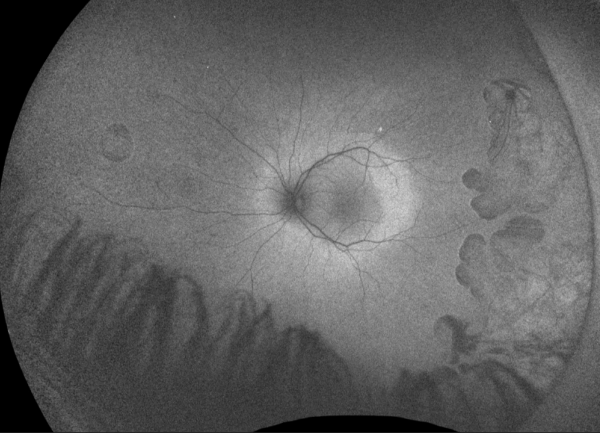

Gyrate Atrophy of the choroida and the retina is a rare autosomal recessive retinal dystrophy characterized by progressive chorioretinal degeneration, early cataract formation and myopia. It is caused by a deficiency in the enzyme ornithine aminotransferase (OAT), which results in a 10- to 20-fold increase in plasma ornithine concentrations. Patients classically present in the first decade of life with nyctalopia, with fundus exam revealing characteristic circular patches of chorioretinal atrophy distributed in the peripheral fundus (Figure 1). As the disease progresses, the atrophic lesions coalesce and advance centripetally toward the posterior pole[1] (Figure 2), correlating with progressive loss of peripheral vision. Macular involvement occurs late in the disease.

Fundus examination early in the disease course shows bilateral patchy, sharply demarcated circular areas of chorioretinal atrophy with hyperpigmented margins in the mid to far periphery (Figure 1). [2] Typically, during the second decade of life, the peripheral atrophic lesions coalesce and spread toward the posterior pole, forming a confluent lesion with a scalloped border at the junction of healthy and diseased retinal pigment epithelium (Figure 2). The remaining healthy RPE in uninvolved areas is hyperpigmented, distinguishing this disease from choroideremia.

Fundus Autofluorescence

Depending on the disease severity, fundus autofluorescence shows either focal or confluent areas of absent autofluorescence, which corresponds with the areas of chorioretinal atrophy seen on fundus exam. These atrophic lesions are commonly surrounded by a sharply demarcated hyperautofluorescent perimeter. The remaining unaffected area, which typically includes the macula, is normal. [16]